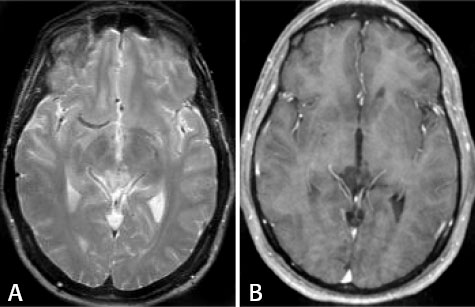

Three months later, a repeat

MR showed the lesion to have decreased significantly. A recent MR exam shows

disappearance of enhancement.